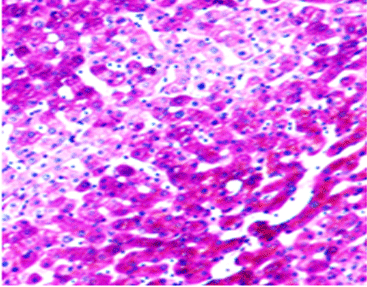

Después de la tinción, la presentación del color de las mucinas ácidas sulfatadas varía desde el marrón violáceo hasta el marrón negro. Las mucinas de los ácidos carboxilados aparecen de color azul. El núcleo celular permanece sin teñir.

20X